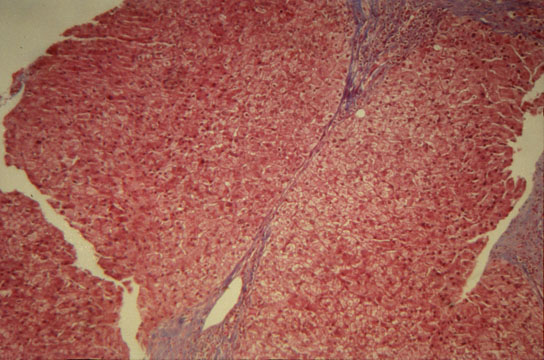

Portal and periportal fibrosis

Fig.68 - PORTAL AND PERIPORTAL FIBROSIS: Fibrous expansion of portal fields with fibrosis extending along the terminal centracinar portal veins assuming the appearance of "stellate" fibrosis. Expansion and branching of normal portal fields must not be confused with pathological portal fibrosis which contains inflammatory cells.